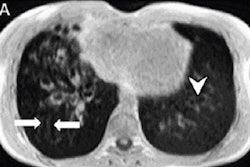

Still image from a video published online showing a dynamic chest radiograph acquired during tidal and deep breathing. Image courtesy of Radiology.Following treatment for pulmonary exacerbation, dynamic chest radiography showed an improvement in the depth of median right (18 mm to 25 mm) and left (13 mm to 19 mm) hemidiaphragm excursion during deep breathing.